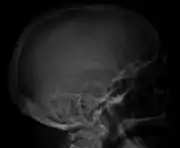

The diagnostic examination of a person with suspected multiple myeloma typically includes a skeletal survey. This is a series of X-rays of the skull, axial skeleton, and proximal long bones. Myeloma activity sometimes appears as "lytic lesions" (with local disappearance of normal bone due to resorption) or as "punched-out lesions" on the skull X-ray ("raindrop skull"). Lesions may also be sclerotic, which is seen as radiodense.[70] Overall, the radiodensity of myeloma is between −30 and 120 Hounsfield units (HU).[71] Magnetic resonance imaging is more sensitive than simple X-rays in the detection of lytic lesions, and may supersede a skeletal survey, especially when vertebral disease is suspected. Occasionally, a CT scan is performed to measure the size of soft-tissue plasmacytomas. Nuclear Medicine Bone scans are typically not of any additional value in the workup of people with myeloma (no new bone formation; lytic lesions not well visualized on nuclear bone scan).

Skull X-ray showing multiple lucencies due to multiple myeloma